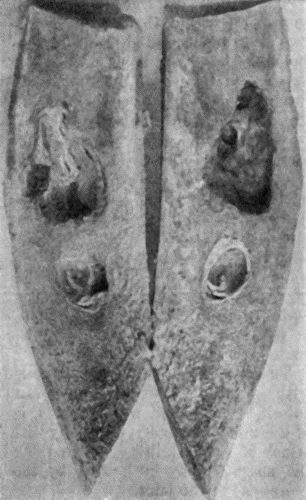

| 19. | Tibia and Fibula, showing changes due to Chronic Ulcer of Leg | 80 |

| 118. | Shaft of the Femur after Acute Osteomyelitis | 444 |

| 119. | Femur and Tibia showing results of Acute Osteomyelitis | 445 |